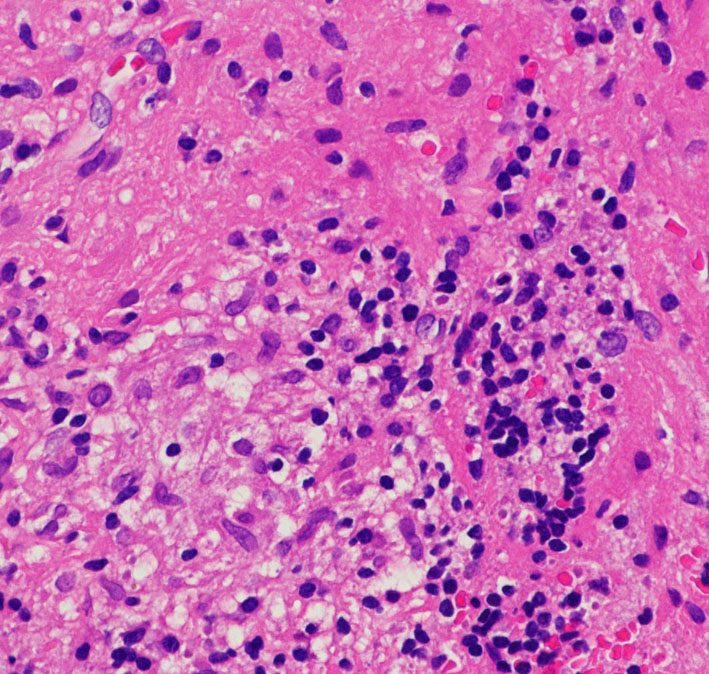

脳梁部分にあった腫瘍の中心部の病理です。炎症細胞浸潤ですがほとんどがリンパ球であり,典型的なtwo-cell patternの所見を示します。

前頭葉深部白質の所見です。大型の疎な核を有する腫瘍細胞が白質内に散在性に浸潤 infiltrationしています。germinoma cells は,脳白質組織内を遊走 migration できる性質を有しています。

GFAP染色です。ある部位では腫瘍細胞が集簇 cluster して白質内に浸潤 invasion しています。germinomaは脳組織に浸潤する腫瘍です。ですから,GFAP養成組織の中に,腫瘍細胞が散在するという所見が得られる時もあります。この時には,GFAP陽性腫瘍であるからgerminomaではないという病理診断が下されてしまうこともあります。要注意です!!